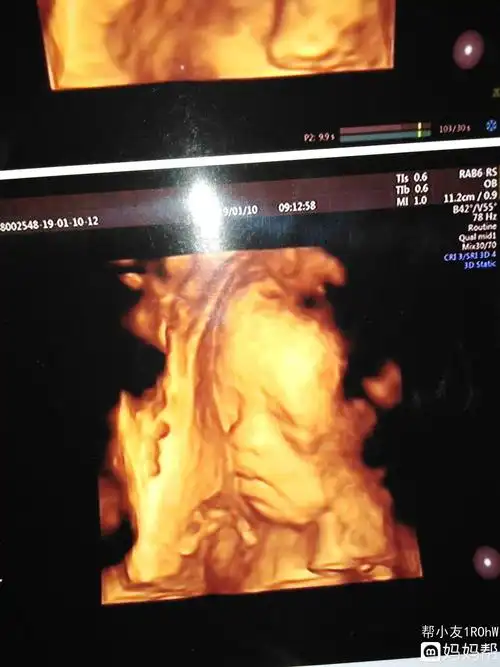

浑厚!六个月四维彩超男孩图"善始善终"-第1张图片-花纹博客